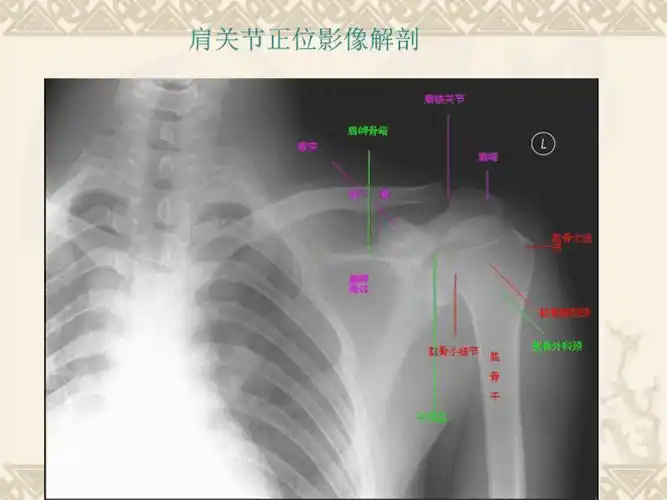

肩关节正位